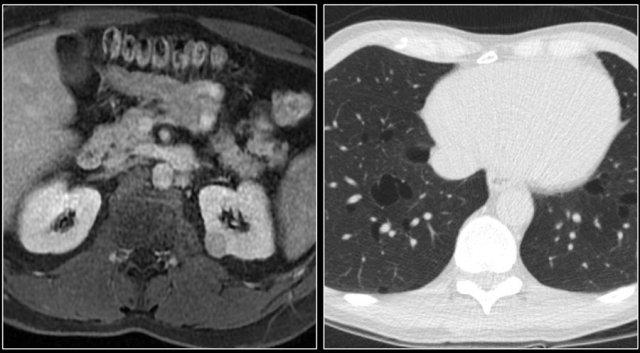

Tổn thương xâm lấn ở cực dưới thận phải, phát triển đáng kể sau sáu tháng, kèm theo hạch bạch huyết lan rộng. Đây được xác định là di căn của ung thư phổi.

Các khối u ác tính nguyên phát thường di căn đến thận nhất bao gồm ung thư phổi, ung thư vú, các khối u đường tiêu hóa và u hắc tố (melanoma).

Di căn thận thường xuất hiện muộn trong tiến trình của một bệnh ác tính đã biết, như một phần của bệnh lan rộng toàn thân.

Trong một số ít trường hợp, di căn thận có thể biểu hiện dưới dạng một tổn thương đơn độc và khó phân biệt với ung thư biểu mô tế bào thận.

Di căn thận thường có kích thước nhỏ, đa ổ và hai bên, với hình thái phát triển xâm lấn.

Các tổn thương này ngấm thuốc nhẹ, kém hơn nhiều so với nhu mô thận bình thường.

Đây là hình ảnh của một bệnh nhân ung thư phổi.

Có một tổn thương di căn ở thận trái và nhiều tổn thương di căn hạch bạch huyết (mũi tên).

Nếu đây là biểu hiện duy nhất, sẽ rất khó để phân biệt với ung thư biểu mô tế bào thận có di căn hạch bạch huyết.